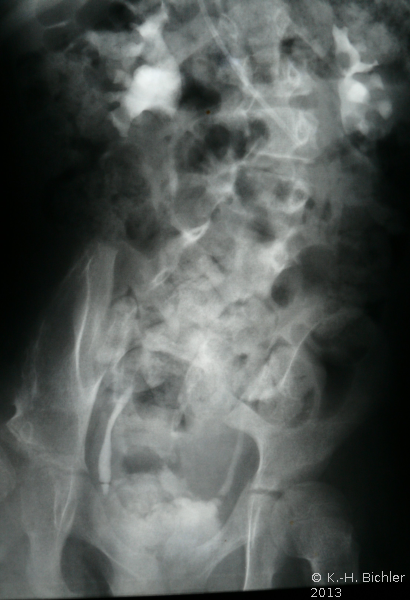

Bei einem 8-jährigen Mädchen mit MMC, ventriculo-peritonealem Shunt und rezidivierenden Harnwegsinfekten ergab die urologische Untersuchung mit Sonographie, AUR, MCU und Urodynamik einen Harnstau II. Grades der linken Niere mit Verplumpung des NBKS (AUR), glatte Abflussverhältnisse rechts (Abbildung 15), VUR links (Abbildung 16b).

Die Urodynamik zeigte eine komplette, nicht ausgeglichene obere motorische Läsion (Abbildung 16a).

Deutliche herabgesetzte Compliance der Harnblase, Wandumbau der Harnblase, eingeschränktes Harnblasenfüllungsvolumen und erhöhter Harnblasendruck. Im Isotopen-nephrogramm:

Nierenfunktion: 85% rechts, 15% links.

Diagnose: Obere motorische Läsion, Low Compliance Blase bei MMC, VUR links mit Refluxnephropathie